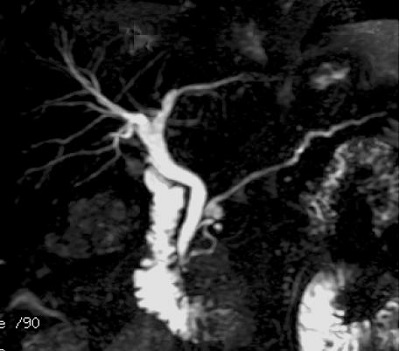

Figure 2. Left = T2 Prep on, right = T2 Prep off